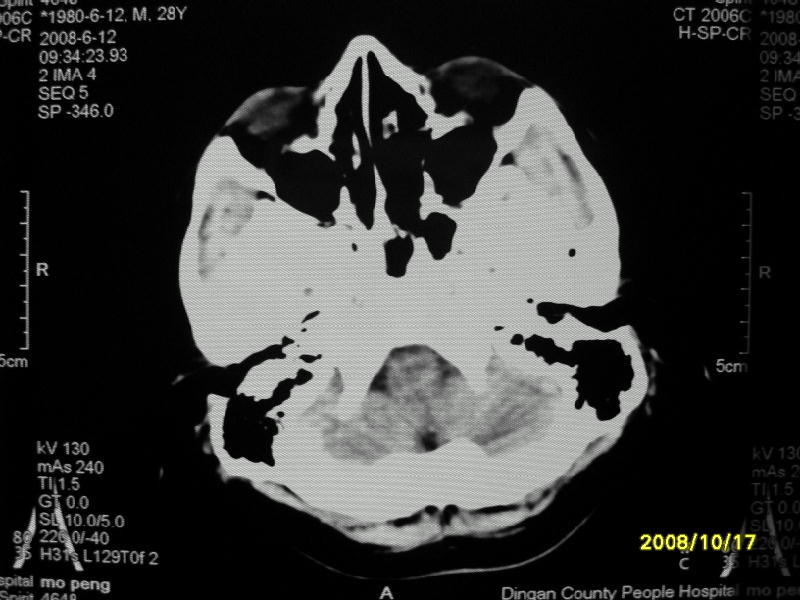

检查名称:     ct颅脑平扫           男     28岁

表现:左顶叶见斑点状致密影。边缘清,大小约0。3*1。0cm,余脑实质密度及灰白质结构示见异常。脑室系统大小,形态,密度未见异常。脑沟。脑裂。脑池未见异常密度影。中线结构无移位。

印象:左顶叶少许钙化灶

左顶叶见斑点状致密影。边缘清,大小约0。3*1。0cm,余脑实质密度及灰白质结构示见异常。脑室系统大小,形态,密度未见异常。脑沟。脑裂。脑池未见异常密度影。中线结构无移位。

印象:左顶叶少许钙化灶。